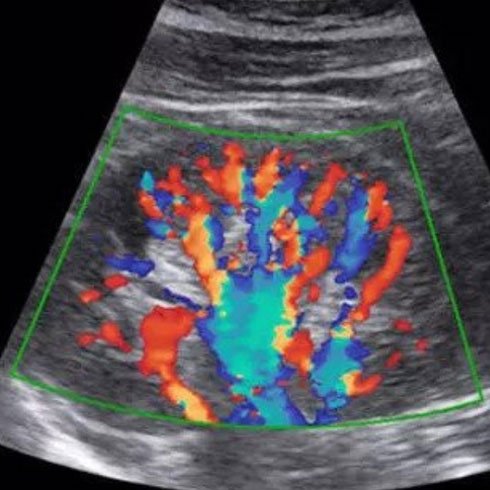

Colour Doppler

Fetal Echo